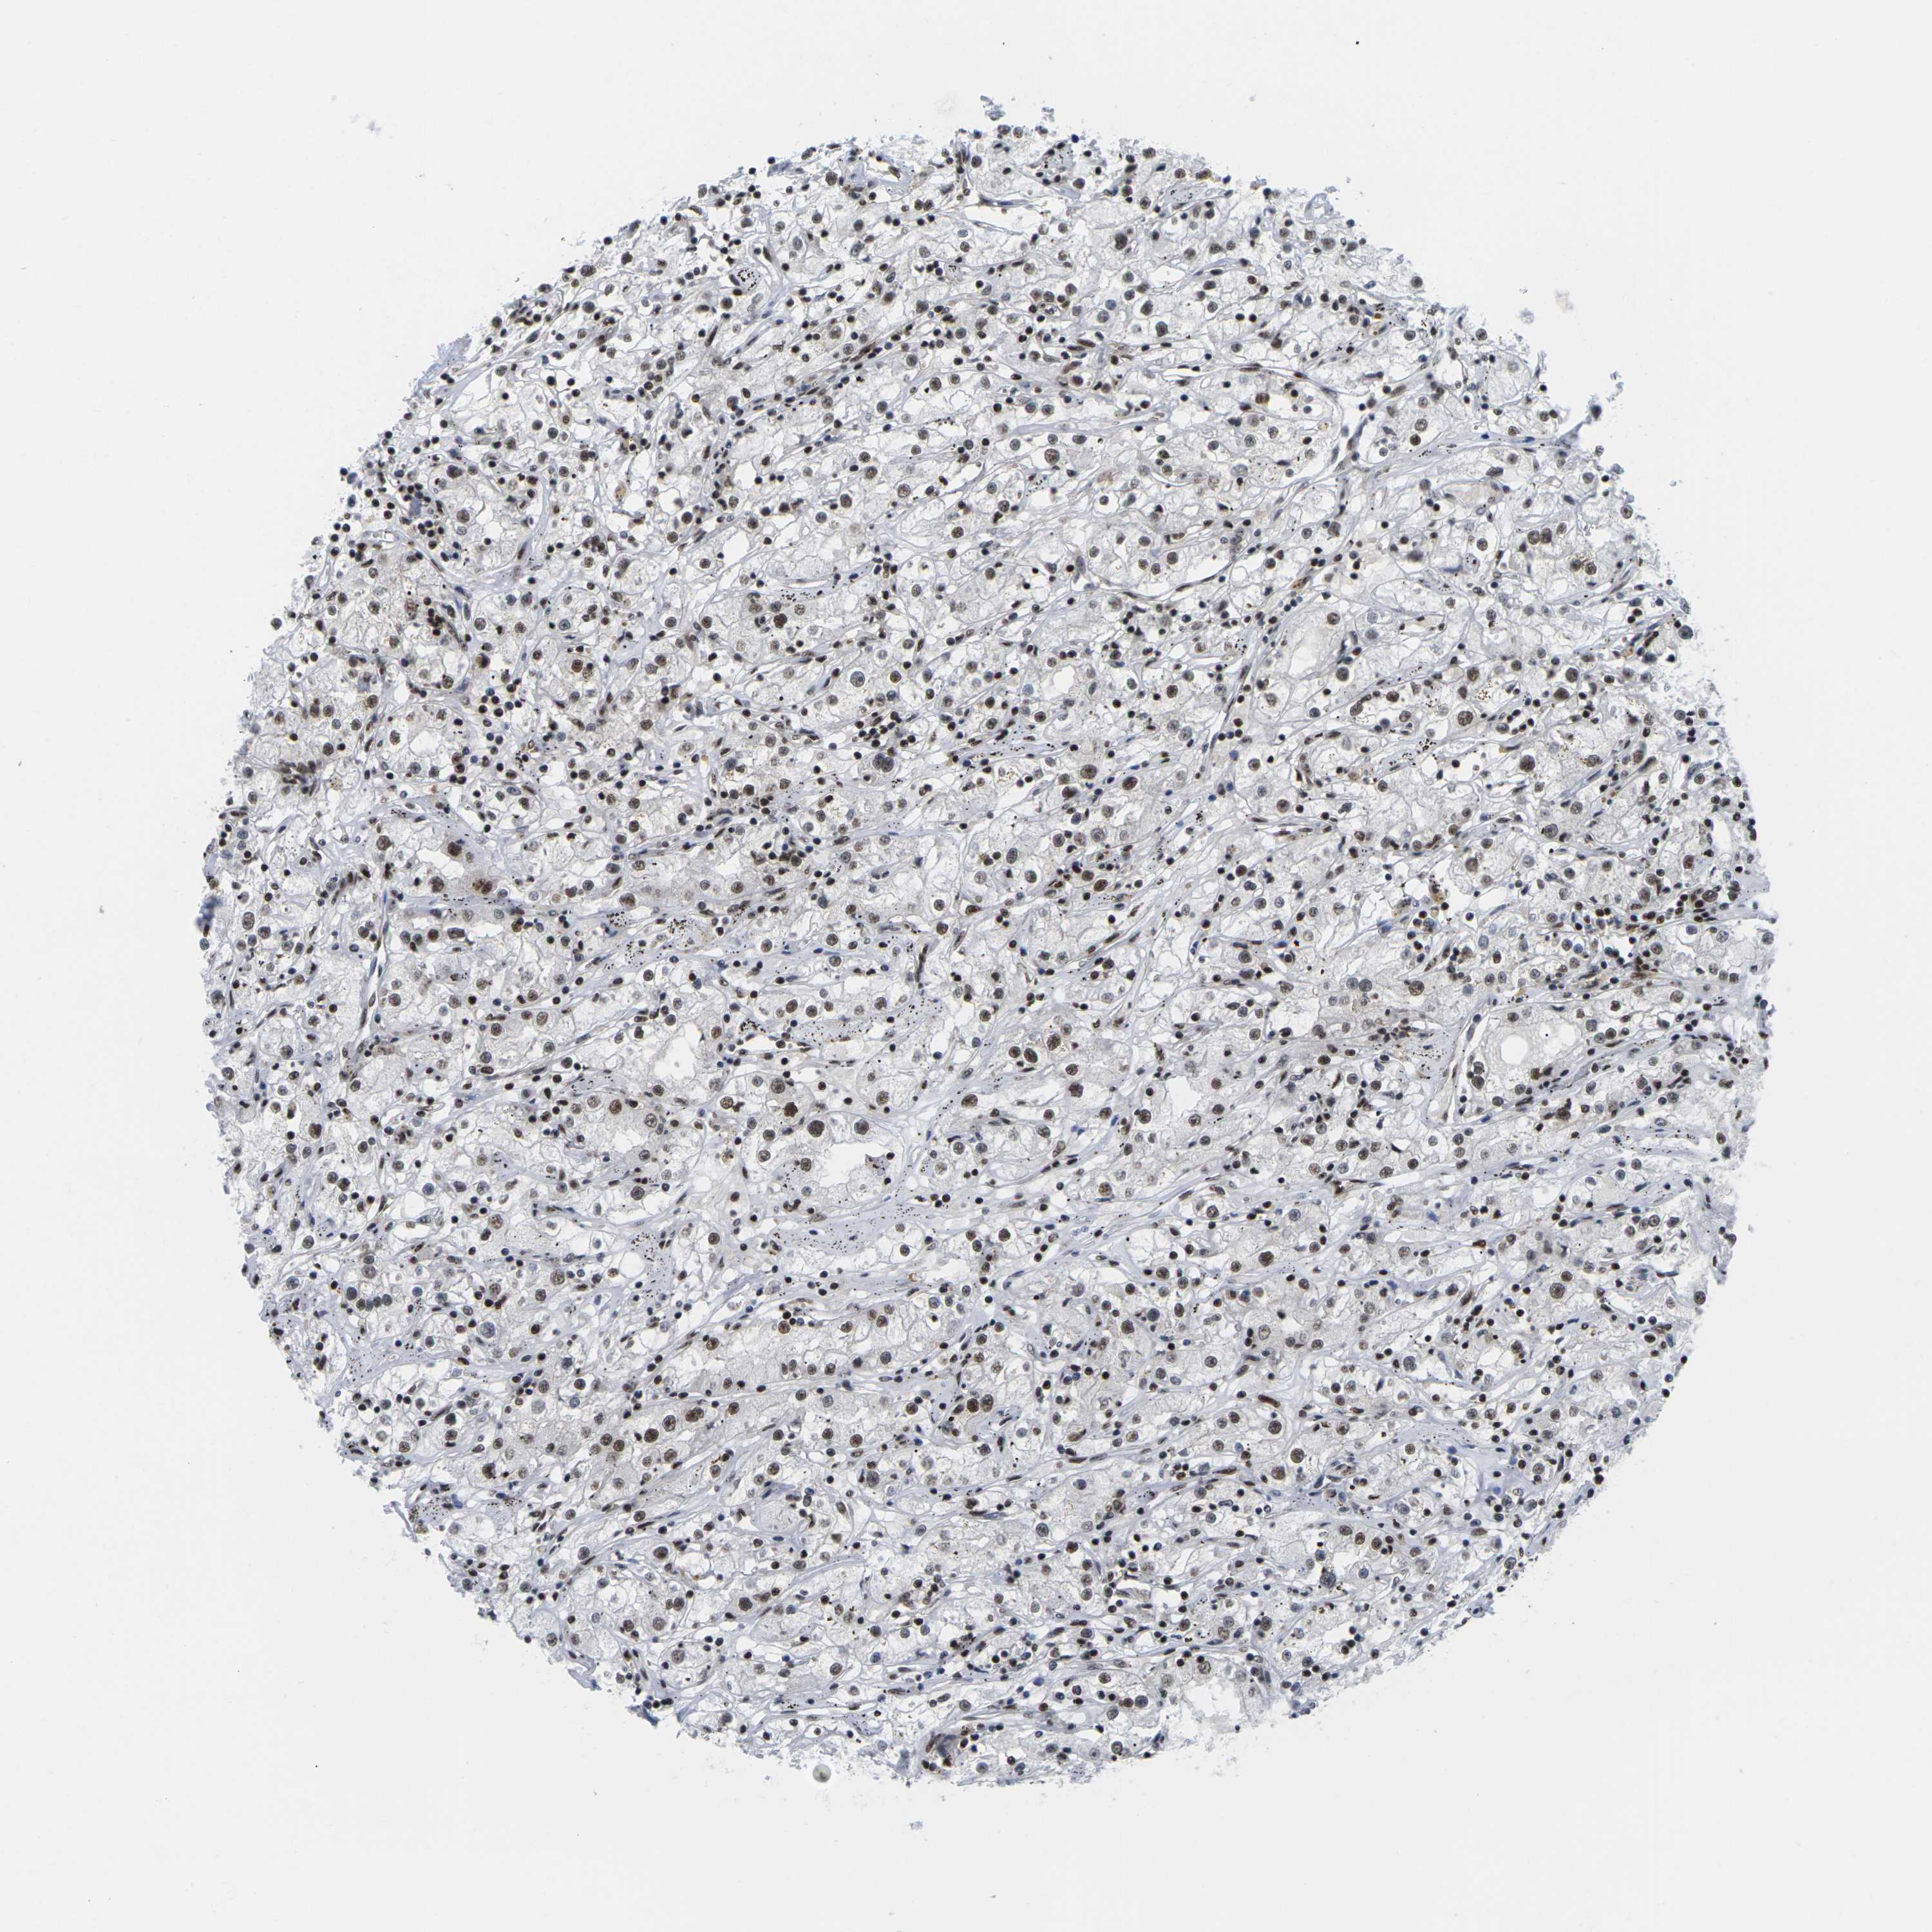

KIDNEY RENAL CLEAR CELL CARCINOMA (VALIDATION) - Interactive survival scatter ploti

The Survival Scatter plot shows the clinical status (i.e. dead or alive) for all individuals in the patient cohort, based on the same data that underlies the corresponding Kaplan-Meier plots. Patients that are alive at last time for follow-up are shown in blue and patients who have died during the study are shown in red.

The x-axis shows the expression levels (FPKM) of the investigated gene in the tumor tissue at the time of diagnosis. The y-axis shows the follow-up time after diagnosis (years). Both axes are complimented with kernel density curves demonstrating the data density over the axes. The top density plot shows the expression levels (FPKM) distribution among dead (red) and alive patients (blue). The right density plot shows the data density of the survived years of dead patients with high and low expression levels respectively, stratified using the cutoff indicated by the vertical dashed line through the Survival Scatter plot. This cutoff is automatically defined based on the FPKM cutoff that minimizes the p-score. The cutoff can be changed by dragging the vertical line or by entering a cutoff value in the square labeled "Current cut-off".

Under the Survival Scatter plot the p-score landscape (black curve; left axis) is shown together with dead median separation (red curve; right axis). Dead median separation is the difference in median mRNA expression between patients who have died with high and low expression, respectively. It is calculated as follows: median FPKM expression of dead patients with high expression - median FPKM expression of dead patients with low expression. This is intended to aid the user in visually exploring custom cutoffs and the associated p-scores and dead median separation.

Individual patient data is displayed and can be filtered by clicking on one or more of the category buttons on the top of the page. Categories describing expression level and patient information include: high, low, alive, dead, female, male and tumor stages. The scale of the x-axis can be toggled between linear and log-scale by clicking on the "x log" button. Mouse-over function shows TCGA ID, patient information and mRNA expression (FPKM) for each patient.

& Survival analysisi

Kaplan-Meier plots summarize results from analysis of correlation between mRNA expression level and patient survival. Patients were divided based on level of expression into one of the two groups "low" (under cut off) or "high" (over cut off). X-axis shows time for survival (years) and y-axis shows the probability of survival, where 1.0 corresponds to 100 percent.

MAGOH is not prognostic in Kidney Renal Clear Cell Carcinoma (validation)

Best expression cut offi

Based on the FPKM value of each gene, patients were classified into two groups and association between prognosis (survival) and gene expression (FPKM) was examined. The best expression cut-off refers the FPKM value that yields maximal difference with regard to survival between the two groups at the lowest log-rank P-value. Best expression cut-off was selected based on survival analysis .

When clicking on this number, the vertical dashed line indicating cut-off, the interactive survival plot, and the Kaplan-Meier curve will be adjusted to show results based on the best expression cut-off.

: 59.69

TCGA RNA samplesi

RNA-seq data is reported as average FPKM (number Fragments Per Kilobase of exon per Million reads), generated by the The Cancer Genome Atlas (TCGA) .

Normal distribution across the dataset is visualized with box plots, shown as median and 25th and 75th percentiles. Points are displayed as outliers if they are above or below 1.5 times the interquartile range. FPKM values of the individual samples are presented next to the box plot.

Average pTPM 73.3

Number of samples 100